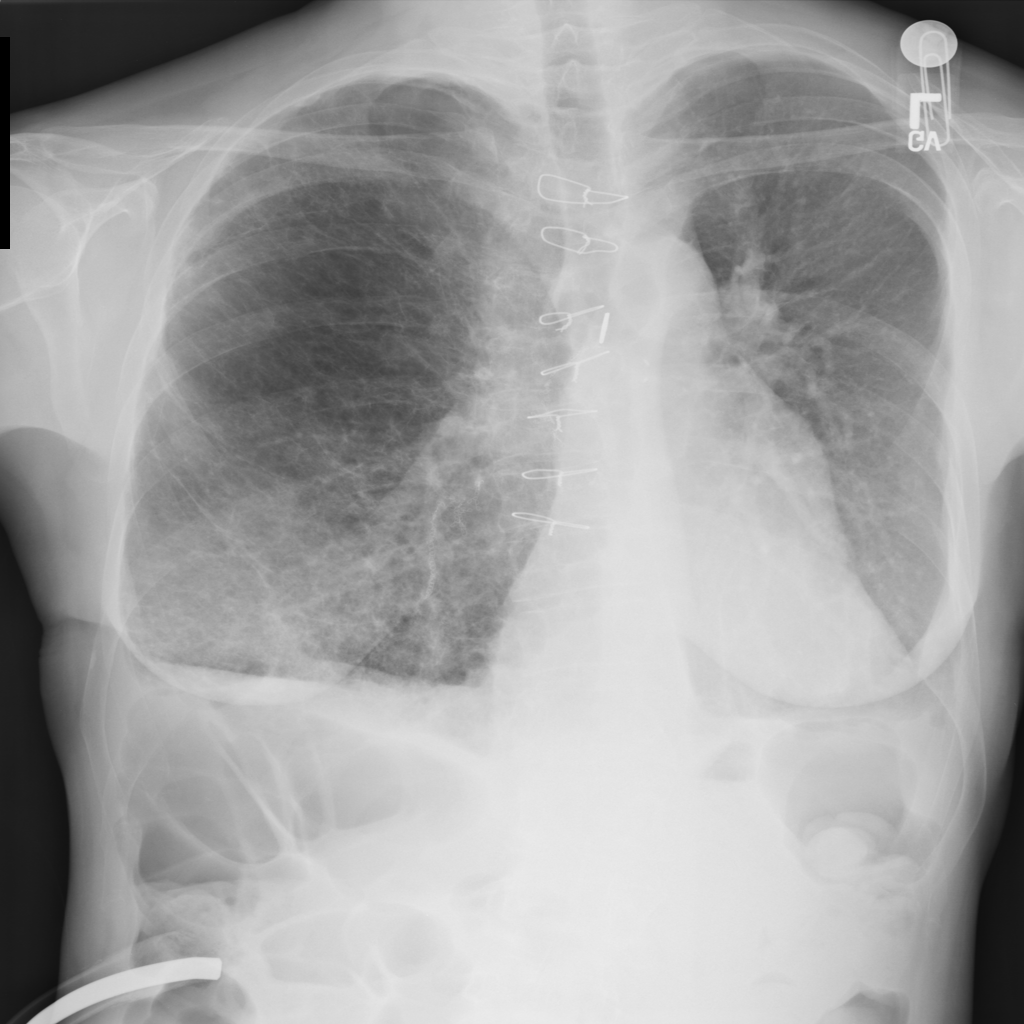

PAT-C77C · IMG-003Fibrosis

PAT-C77C · IMG-003

PA